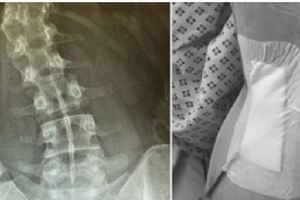

她PO出「剛做完脊椎側彎手術」恐怖照,背後「2根支架直接從肉裡捅出來」網嚇:不敢翹腳了!